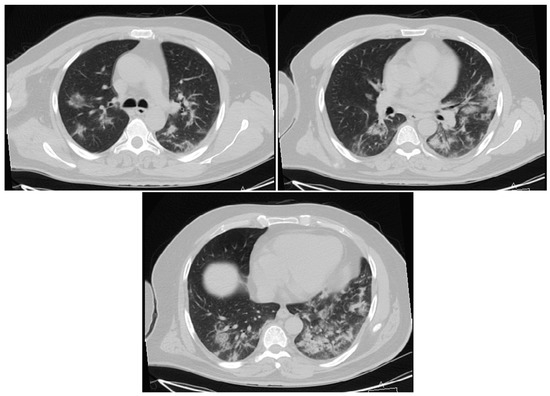

3.1.1. Cases Reports from Iran

Case 1

Case 2

Case 3

Case 4

Case 5